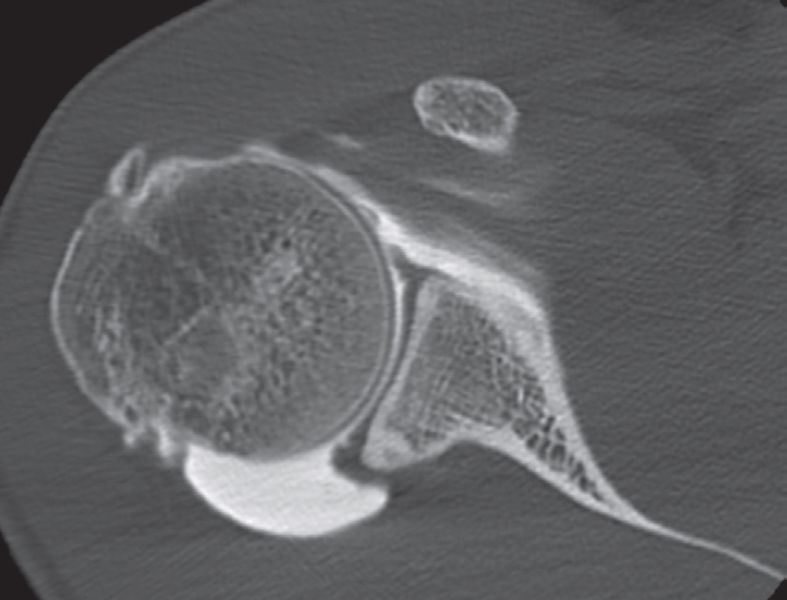

Computer tomography arthrogram showing (on the upper axial slices) labral tears and articular rotator cuff lesions.